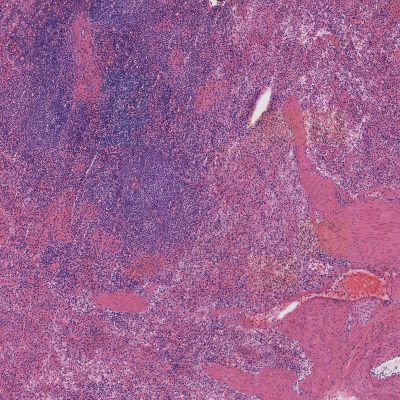

Spleen without FineFIX

Without FineFIX

Spleen with FineFIX

With FineFIX processing